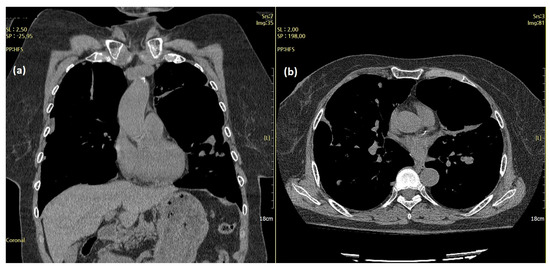

A 70-year-old woman visited the clinic complaining of acute cough and dyspnea in April 2017. A chest X-ray and chest computed tomography (CT) revealed pneumothorax in the left chest and multiple nodules in both the lungs (Figure 1).

Figure 1.

A chest computed tomography (CT) features of the lung masses. A chest CT (April 2017) showed pneumothorax in the left lung and multiple masses in both lungs. The amount of pneumothorax was small (solid arrows) because CT was performed after the chest tube (dotted arrows) was inserted and stabilized.